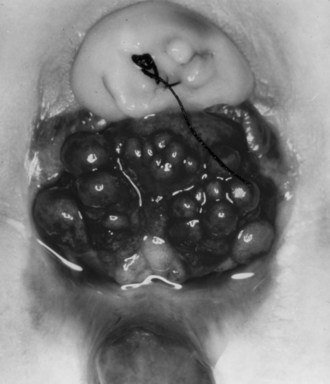

Cloacal exstrophy usually includes an open and everted intestinal segment situated between two hemibladders, an omphalocele and a blind ending tailgut with an imperforate anus. The pubic symphysis and the rectus muscles are widely separated. The phallus is bifid, and the scrotum or labia are split and laterally displaced. In girls the vagina is bifid with two uteri. Given that cloacal exstrophy encompasses abnormalities of the genitourinary, gastrointestinal, and musculoskeletal systems, and often the neurologic system, it is not surprising that a wide range of variants from the classic presentation have been reported. The treatment of cloacal exstrophy has evolved from palliation of an almost universally fatal disorder into complex genitourinary and gastrointestinal reconstruction and a near-normal life span.